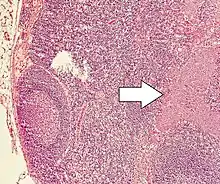

| Micrograph of a neuroendocrine tumor. H&E stain | |